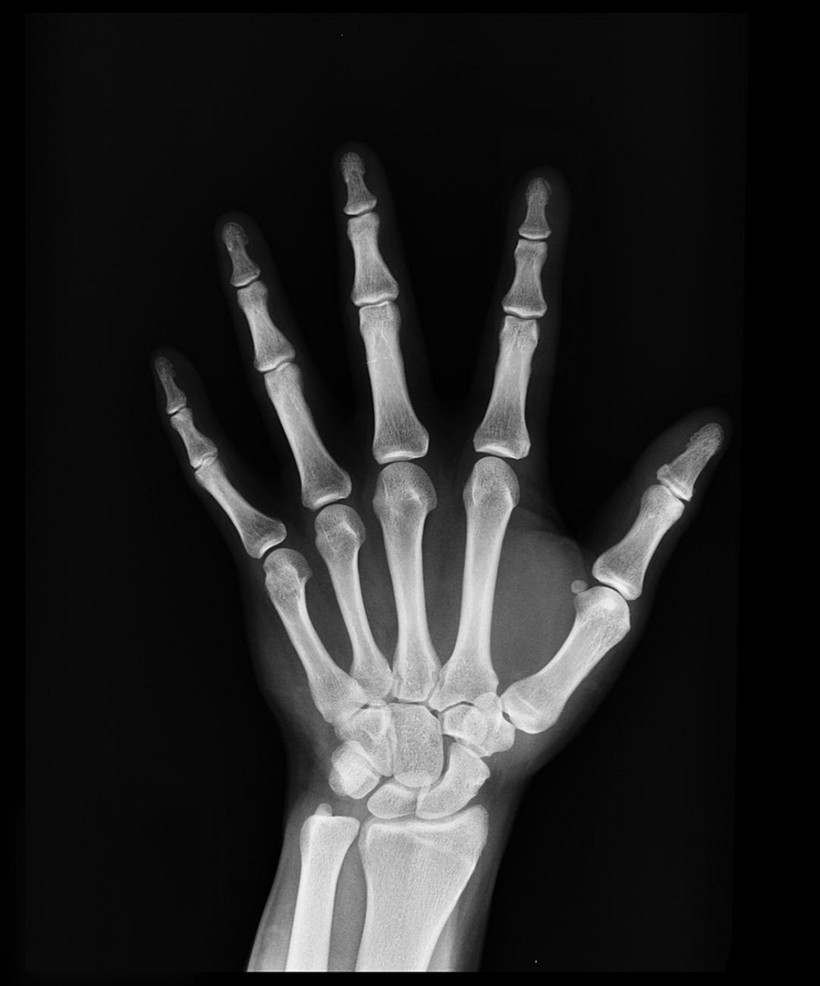

Kırılgan kemik yapısı kan kanseri habercisi olabilir! - Resim: 4

İstanbul Tıp Fakültesi Öğretim Üyesi İç Hastalıkları ve Hematoloji Uzmanı Prof. Dr. Sevgi Kalayoğlu Beşışık, bir kan hastalığı olan multipl miyeloma ile ilgili olarak yaptığı açıklamada, hastalığın kan üretiminin yapıldığı kemik iliğinden köken alan ve bağışıklık sistemi hücresi plazma hücrelerinin kanser hücrelerine dönüşmesiyle ortaya çıktığını söyledi.